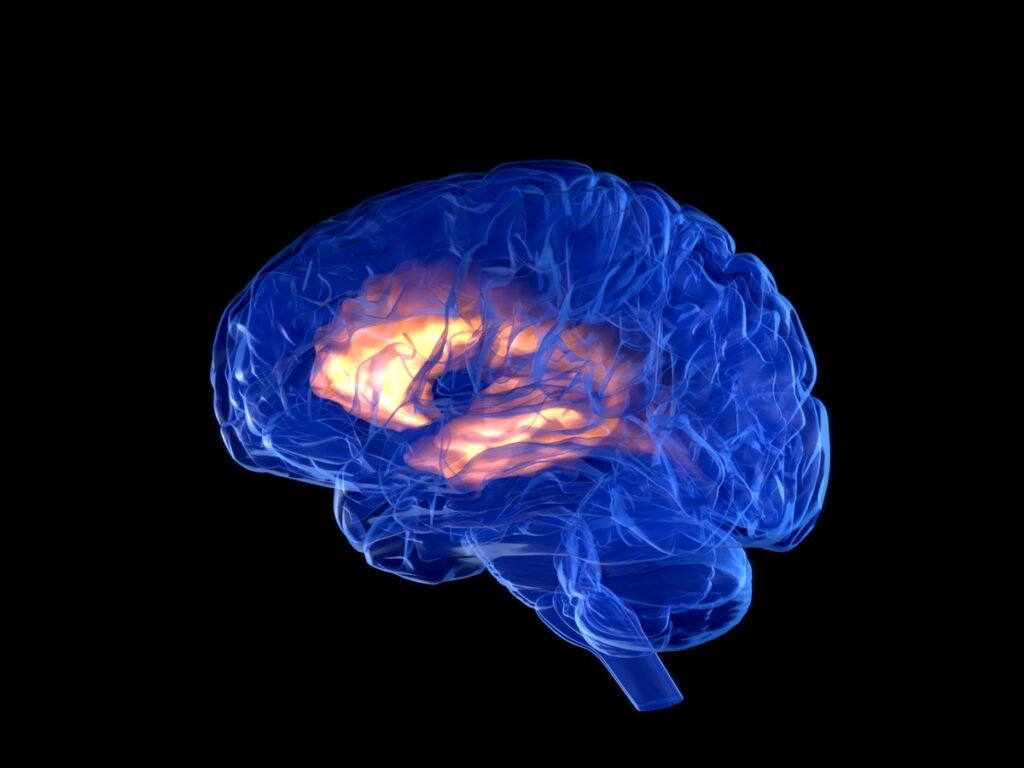

Krehbiel, who tested the first participant in the deep brain stimulation (DBS), was trembling and essential vibration (then other symptoms and conditions). The new adaptation system automatically adjusts the level of stimulation by a person’s brain signals. Received at the end of February FDA approval Parkinson’s disease “Based on the results of the international multiple judgment, participants took part in four areas in four areas: USA, Netherlands, Canada and France.

This technology is suitable for anyone in Parkinson, and is not those in clinical trials, Helen Bronte-Stewart said, the last newest test world researcher specializing in global researchers and Stanford medicine movement mixtures. “Like the cardiac value of the heart responds, the brain stimulation adapter uses a person’s brain signals to control the electric pulks,” says Bronte-Stewart. “This is more personalized than older DBS methods, accurate and more efficient.”

“Traditional dbs do not always add constitutive symptoms of the Parkinson’s disease,” The Brains Seach-Simulation program of the Parkinson, the Adjustment of the DBS, “the goal is to adjust real time to improve the symptom less effective, less side effects and quality of life.”

“Our personalized treatment can control vibrations for a person living with Parkinson,” says Ashwiini Sharan, a Medstronic Neuromodulation Neuromodululation Medstronic Manufactures this technology. Located under the chest skin, a DBS device transports electrical signals to a brain that controls movements.